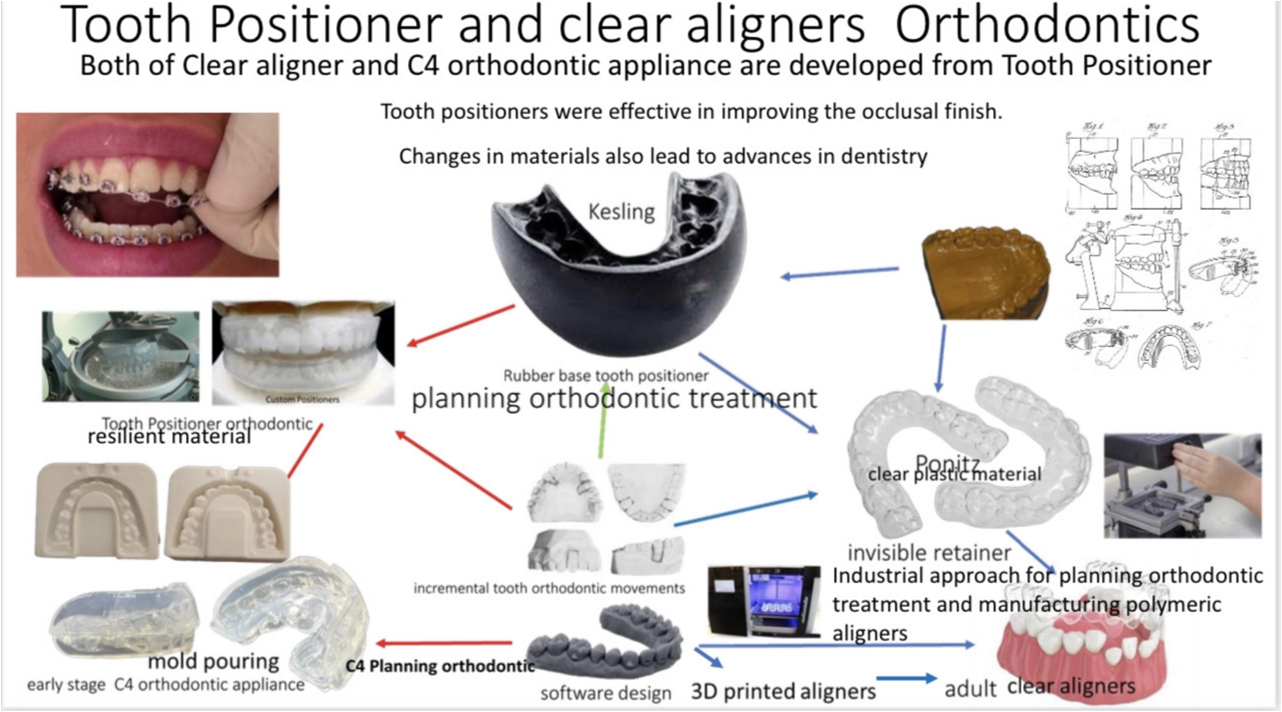

COMiP braces and invisible braces have the same origin. As for the Tooth positioner invented by Keslin in 1942, it was initially used as a maintainer after the correction, Because the Tooth positioner has the ability to position the corrected teeth, adjust the angle and obtain more occlusal contact, Therefore, it can help with tooth movement and correct minor dental differences. Subsequently, multiple sets were used to incrementally move teeth, and this feature was developed into Tooth positioner orthodontic.

The traditional tooth positioner is made in the same way as dentures. According to the upper and lower bite records, the upper and lower articulators are used to make braces that the upper and lower parts can bite together.

In the 1960s, vacuum thermoplastic materials appeared to make maintainers. This method was simpler and more convenient than the Tooth positioner used before. It did not require an articulator and was manufactured directly on the plaster model. The method of using vacuum thermoplastic materials to make retainers is still in use today.

In 1970, Ponitz developed early translucent correction based on the concept of Tooth positioner orthodontic at that time. Until Hermit Beauty uses digital design of teeth and 3D printing to produce invisible braces, Slight increments and multiple pieces allow for more space movement, fulfilling Keskin’s wish back then. However, this correction method lacks the interactive movement of the upper and lower bites. Therefore, it can effectively align the teeth, but it cannot accurately align the upper and lower bites.

The technology of the 21st century, the application of oral scanning and orthodontic software, has given the traditional Tooth positioner orthodontic a glimmer of hope. Nowadays, the teeth can be arranged neatly in the same way as invisible braces, and then based on the characteristics of the Tooth positioner, braces with gnathological positioner can be made based on the teeth arranged in a type of occlusal position.

The advantage of this designed Tooth positioner silicone braces is that, like invisible braces, the teeth are moved through the power of vertical occlusion, and the teeth can be arranged according to the ideal occlusal relationship.

COMiP uses the characteristics of Tooth positioner to establish the occlusion relationship of the Maximal Intercuspal Position (MIP) of Class I occlusion. This position is also called Central Occlusion (CO). During the mixed dentition period, it guides the tooth alignment of the upper and lower jaws. The method of positioning is used to guide the growth and arrange the teeth. Finally, the teeth are replaced and the teeth are arranged neatly.

- Speaking of clear aligners, of course we have to mention the earliest founder, Dr. Kesling. In 1945, he invented the [Tooth Positioner] device, which is actually the predecessor of Invisalign. He used this device to After fine-tuning, the teeth that were slightly lost were corrected and reset, but the function only stopped there and no further extension was done.

- It wasn't until 1997 that Zia Chishti, a student studying for an MBA at Stanford University, found that her teeth were slightly out of place after being straightened, so she went to a doctor to make adjustments. She accidentally discovered this device that could move teeth. This little idea This opened up the extension of his unlimited creativity, so he found his classmate Kelsey Wirth to co-found a new start-up company Align Technology to develop the Invisalign system. In 1998, he obtained FDA certification, and in just four years, the company It was successfully listed in 2001, attracting more capital injections and accelerating the formation of the entire invisible correction related technology.

- By 2015, Align Technology hired professional manager Joseph M. Hogan to manage it. The original founder, Zia, successfully established three IPO companies after leaving Align Technology, and later engaged in consulting services related to AI consulting. This person is undoubtedly a business wizard. Even though he is a billionaire, he still devotes his passion to founding start-ups with the latest technology.

Dr.Kesling, the Grandfather of Invisible Correction

The two founders of Align Technology Invisalign (the boy above is the CEO, Zia Chishti, and the girl is the president, Kelsey Wirth)

Breakthrough in the development of Invisalign technologyPeople often ask why such a powerful technology like Invisalign has only become more common in Taiwan in recent years? There are mainly two reasons:The first is the development of technology. Let’s first look at the development scale of Invisalign. In the early years from 1999 to 2009, there were one million cases, three million cases in 2015, four million cases in 2016, and 2017. Five million cases per year, the growth rate has increased significantly since 2015. The main reason is the establishment of infrastructure integrity + the popularization of technologies such as 3D Printing.

- The first is the development of technology. Let’s first look at the development scale of Invisalign. In the early years from 1999 to 2009, there were one million cases, three million cases in 2015, four million cases in 2016, and 2017. Five million cases per year, the growth rate has increased significantly since 2015. The main reason is the establishment of infrastructure integrity + the popularization of technologies such as 3D Printing. Take a look at the Hype Cycle for Emerging Technologies surveyed by Gartner, 2012: Many technological advances in it can correspond to the jump of Invisalign, such as: the popularity and speed of the Internet, which reduces the round-trip time of data; 3D The maturity of printing machines has reduced manufacturing costs and improved accuracy; digital oral scanning has made this treatment no longer regional and can be easily transmitted globally; algorithms + big data have established SOPs for orthodontic treatment, which is a new technology Changed the development and direction of the orthodontic world.

- The second is the maturity of invisible braces technology. In fact, I was exposed to Invisalign in 2011, but the technology at that time could only be limited to treating "slightly messy teeth". In addition, it was expensive and difficult to use. It is convenient (for example, the impressions need to be sent abroad, the travel time is long, etc.), so not many doctors are willing to try it.

- It was only in 2013, when Invisalign Corporation officially established a branch in the Asia-Pacific region, that it began to pay attention to the treatment and research and development of abnormal bites in Asians. The G5 treatment for deep bites in 2014 and the G6 molar extraction treatment in 2015 have slowly begun to attract the attention of doctors in the Asia-Pacific region.

- Regarding the shortcomings of Invisalign discussed in PTT or on the Internet, most of the opinions that Invisalign is only suitable for the correction of slightly messy teeth were made before 2016 (otherwise, the dentist does traditional correction and does not I am familiar with Invisalign and have not kept up with the latest developments). In the past few years, as the technology related to invisible braces has matured, more and more doctors have published treatment methods and improvements for difficult cases. Everyone is constantly optimizing the collected information. Scientific data is used to study treatment patterns for various abnormal bite types, gradually establishing a stable and predictable process.

- With talents, infrastructure, market trends, technological development and other factors in place, it is conceivable that the positive cycle of optimization will be faster, and the difficulty and stability of treatment will also be greatly improved.

- The principles of Invisalign and Invisalign come from a hundred years of accumulated knowledge and experience in traditional orthodontic biomechanics. The purpose of Invisalign and braces is the same as that of braces, but it is accomplished through different techniques and media.